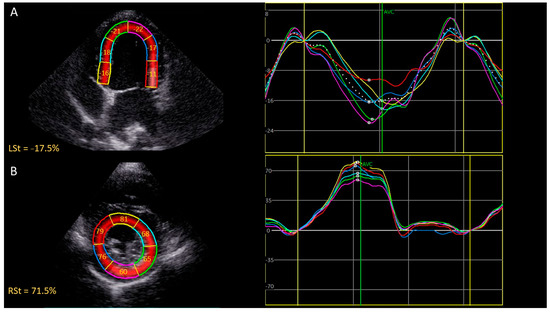

2.2. Echocardiographic Measurements

| LSt | Peak systolic regional longitudinal strain |

| CSt | Peak systolic regional circumferential strain |

| RSt | Peak systolic regional radial strain |